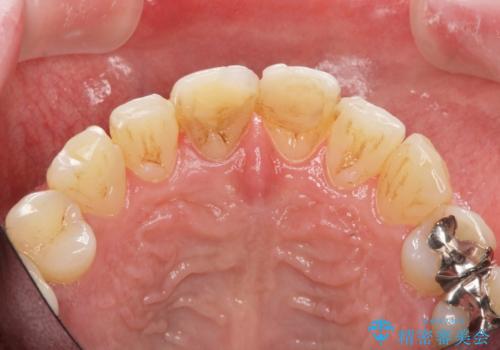

前歯の変色を改善 オールセラミック治療

感染の疑われる根管内に対し再度根管治療を行い、セラミッククラウンを作製することで審美性の回復します。

目立つ前歯の審美性が改善したことで見た目を気にせず笑えるようになった。との嬉しい感想をいただくことができました。